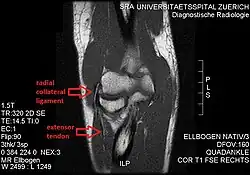

The radial collateral ligament (RCL), lateral collateral ligament (LCL), or external lateral ligament[Explain 1] is a ligament in the elbow on the side of the radius.

- the radial collateral ligament [proper] (RCL), from the lateral epicondyle to the annular ligament deep to the common extensor tendon[1]